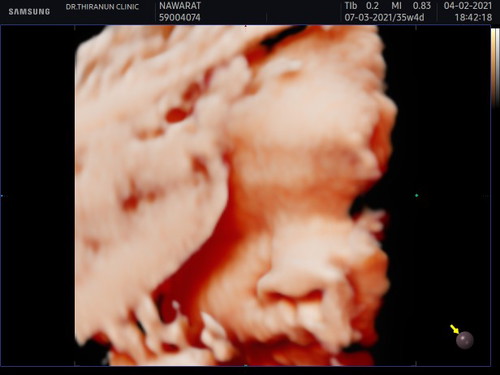

35+4 จะ9เดือนละหมอบอกน้องน้ำหนัก2000 กรัม กังวลมากค่ะ บ้านอื่นน้องน้ำหนักเป็นใงบ้างค่ะ

ซาวด์ตอน34+2week น้องหนักแค่2070 เหมือนกันค่ะ หมอบอกเล็กไปนิด แอบเครียดเหมือนกันค่ะ น้ำหนักแม่ก็ไม่ขึ้นเลยมา4เดือนแล้ว 🥺